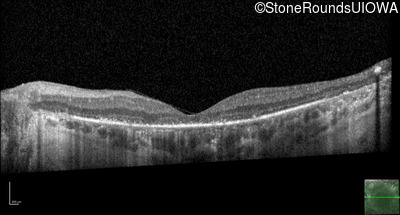

Optical Coherence Tomography - Left - 10/120 -1

Exemplar / OCT Stack

OCT Stack